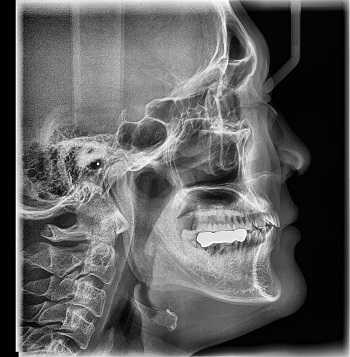

Принцип работы рентгеновского аппарата заключается в том, что рентгеновские лучи, проходя через разноплотную среду исследуемой области, по-разному ослабляются: более плотная костная ткань в значительной степени поглощает рентгеновское излучение, менее плотная подкожно-жировая клетчатка ослабляет его в небольшой степени, а воздух, содержащийся в околоносовых пазухах или легких, не задерживает совсем. Эти неравномерно ослабленные пучки рентгеновских лучей, попадая на светочувствительный слой пленки, формируют рентгенограмму — изображение, которое отображает все структуры исследуемой области, наслаивая их друг на друга. При этом получаемый снимок позволяет определить форму, размеры и строение исследуемой области, выявить или заподозрить структурные нарушения, а исследование в двух или нескольких проекциях позволяет определить локализацию выявленных изменений. Чаще всего рентгенография используется для исследования костей, легких, почек, кишечника.